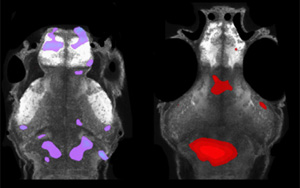

昆士蘭大學(xué)領(lǐng)導(dǎo)的一項(xiàng)研究表明,肝細(xì)胞會(huì)影響人體內(nèi)部的生物鐘,而此前人們認(rèn)為生物鐘完全由大腦控制。昆士蘭大學(xué)分子生物科學(xué)研究所的fracimdsamric Gachon副教授和法國(guó)巴黎城市大學(xué)/CNRS的Serge Luquet博士及其合作者已經(jīng)證明,移植了人類(lèi)肝細(xì)胞的小鼠具有改變的晝夜節(jié)律。這項(xiàng)研究發(fā)表在《Science Advances》雜志上。